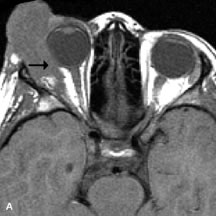

Lymphomas have MRI characteristics similar to those of inflammatory lesions in that they are hypointense to fat and isointense to muscle on T1-weighted images (Fig. 22). They may appear hyperintense to fat on T2-weighted images, perhaps owing to less fibrosis than that seen in orbital inflammatory pseudotumor, although this is not a consistent finding.31,50,66 Lymphoid tumors typically enhance moderately after contrast injection. Unfortunately, studies have shown that tumor density and homogeneity are similar between inflammatory and malignant orbital infiltrates, and MRI cannot differentiate these lesions.72,73

Fig. 22. A and B. T1- and (C) T2-weighted MR scans demonstrate a poorly defined multicompartmental mass enveloping the lateral rectus, superior rectus, and levator palpebrac superioris muscles. The lesion is isointense to brain on T1- and T2-weighted scans, as is typical for highly cellular neoplasms. D. Postcontrast fat-suppressed T1-weighted scan demonstrates intense enhancement of the infiltrating intraconal and extraconal tumor.